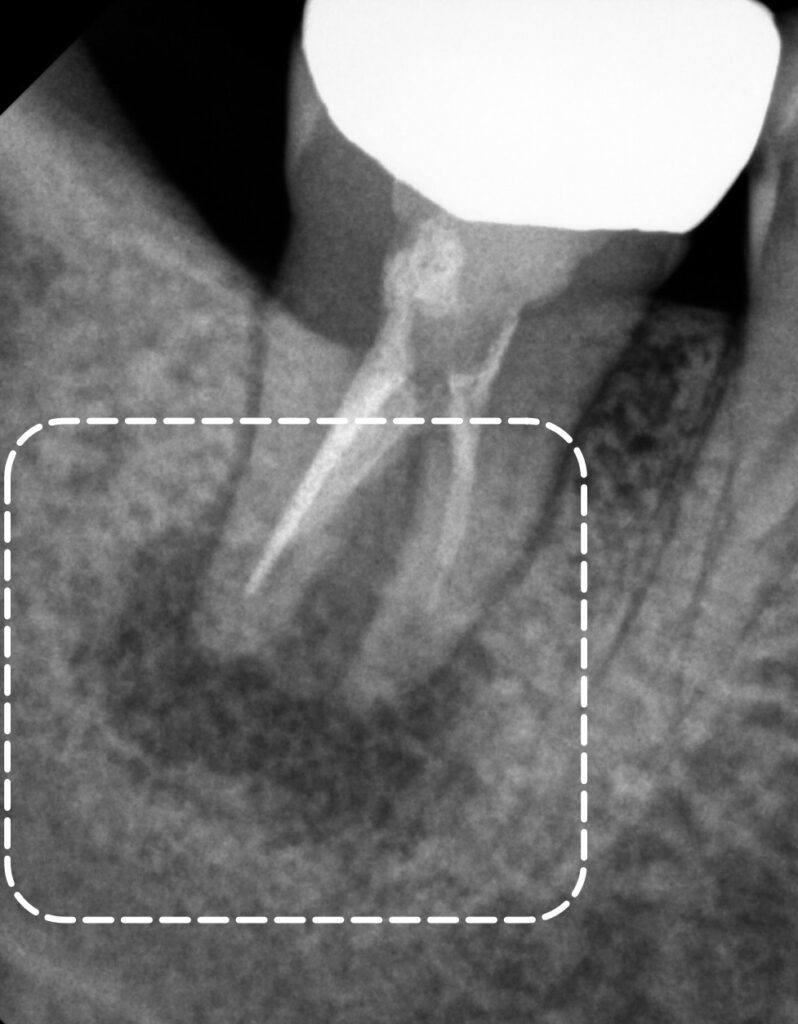

신경치료 후 6개월이 지난 시점에서

치주낭 깊이는 3mm 정도로 개선되어도

완전히 치유되지 않았다면,

가끔 부종이 나타날 수 있는데요.

이때에는 꼭 재 검진을 받아야 됩니다.

치근단 사진을 보면

치아 뿌리 끝 염증이

치유되지 않은 것을 확인할 수 있습니다.

이는 치근과 치근 사이,

특수한 해부학적 구조나

접근하기 어려운 부위의 감염이

여전히 남아있을 가능성을 뜻합니다.